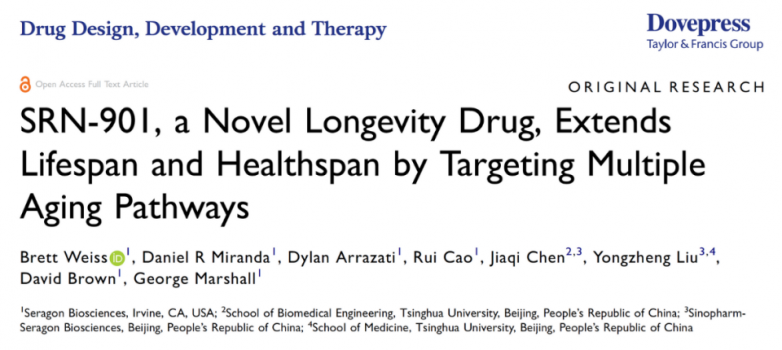

中美科学家发布重磅成果:SRN-901增寿33%,越老越健康

日前,一项中美科学家联合完成的突破性研究,直接扔出一枚重磅炸弹——一种名为SRN-901的新型衰老干预药物,在动物试验中让中年试验动物剩余寿命猛增33%,肿瘤发病率狂降30%,连外表都肉眼可见地变年轻